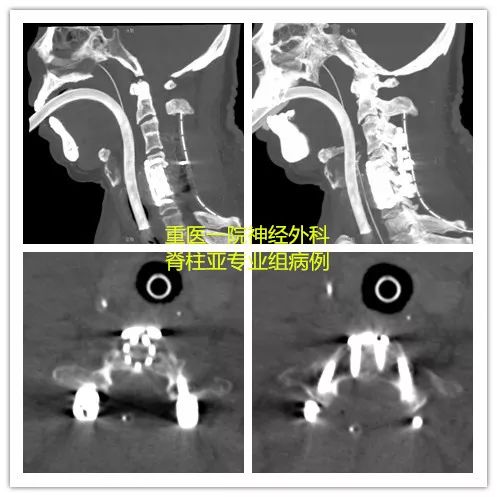

术后影像

术后复查CT可见椎管减压充分,内固定系统固定在位。